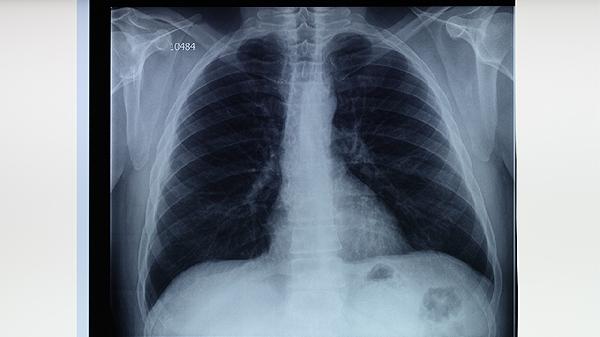

五、支气管炎

清肺抑火丸可用于急性支气管炎的辅助治疗。支气管炎患者常出现咳嗽、咳痰、胸闷等症状,与气道炎症反应有关。药物中的苦杏仁、桑白皮等成分能缓解气道痉挛,减轻炎症反应。患者需注意休息,避免刺激因素加重病情。